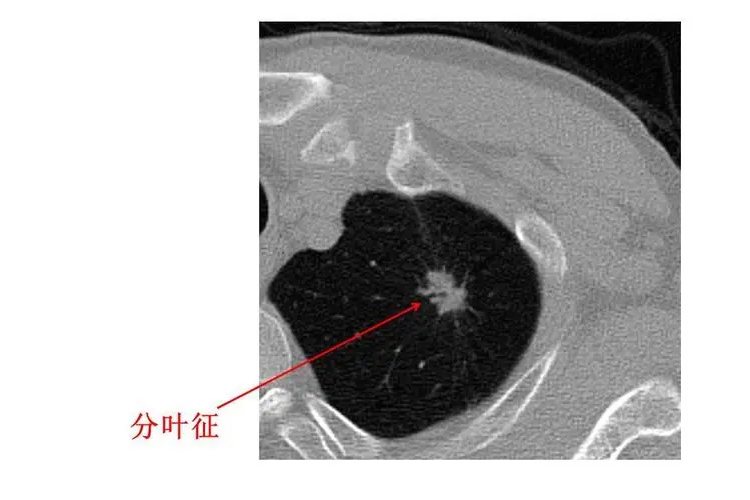

大多数良性肺结节的形态为圆形或类圆形,与恶性实性结节相比,恶性肺结节出现不规则形态的比例较高;毛刺征、分叶征常提示恶性的可能,而良性肺结节多数无分叶,边缘可有尖角或纤维条索等,周围出现纤维条索,胸膜增厚等征象;病灶周围的胸膜凹陷征与血管集束征亦为鉴别良恶性常见且有价值的特征。